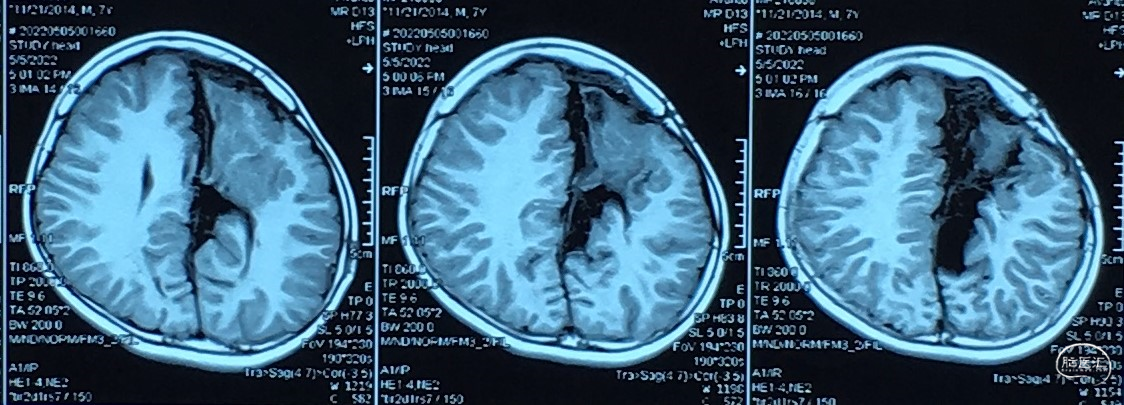

7岁 小学一年级,成绩较差、余无神经功能障碍

脑组织形态发育接近正常

但是,7岁某一天开始,间断头痛伴呕吐:

“颅内囊肿分流术后7年、间断剧烈头痛伴呕吐一月余”

诊断、处理???

1、分流管依赖(裂隙脑室)综合征。

2、病因:复张(发育)脑组织顺应性降低。

3、颅内压往往显著升高、间断剧烈头痛。

4、脑表面蛛网膜下腔间隙小、无法分流CSF。

5、腰大池腹腔分流术:多数病例可以缓解症状。